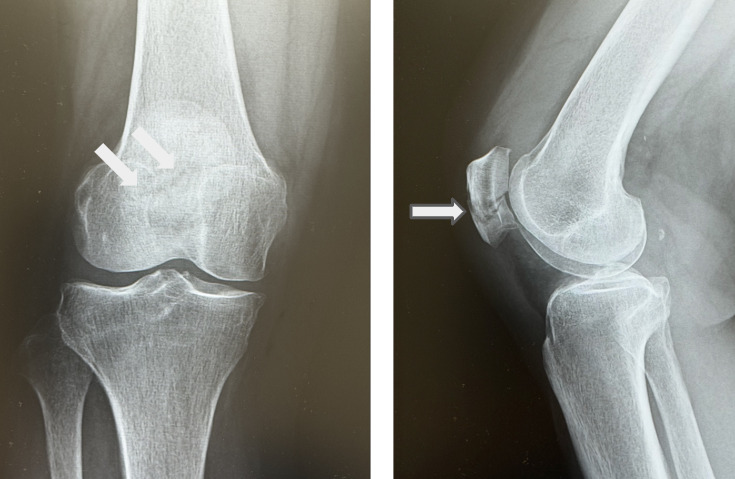

画像検査はX線3方向(正面・側面・スカイライン)が基本です。とくにスカイライン像は、縦骨折では側面像だけでは判断できないことがあるため、膝蓋骨骨折を疑う場合に有効です。骨折型の目安としては、横骨折が約半数、縦骨折と粉砕骨折がそれぞれ約4分の1とされます。

膝蓋骨骨折の治療は、骨折型(縦骨折・横骨折・粉砕骨折)と、特に関節面の転位量を軸に保存療法か手術療法かを選択します。一般に、関節面の転位が小さい場合(目安として2 mm未満)は保存療法が選択されやすく、転位が大きい場合(2 mm以上)や横骨折・粉砕骨折では手術となることが多いです。